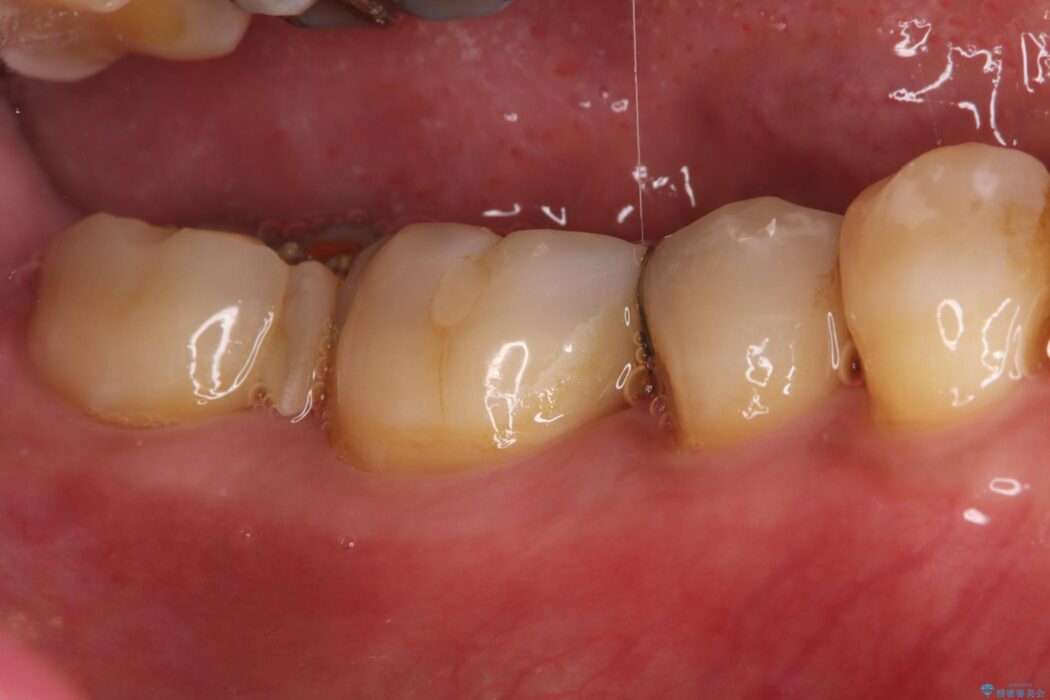

検査の結果、残存歯質が少なく破折リスクが高いため、歯全体の補強が必要と診断しました。強い咬合力に耐えられるよう、適合性と強度に優れたPGAクラウンによる修復を計画しました。これにより、二次カリエス(虫歯の再発)や破折を防ぎ、奥歯の機能を長期的に安定させます。

欠けた奥歯を土台から整え、金主成分の「PGAクラウン」で修復しました。PGAクラウンは、金を主成分とする合金でできており、非常に優れた特性を持っています。

欠けてしまった歯の構造的な弱点が解消され、患者様は硬いものでもしっかりと噛める、安心で機能的な奥歯を取り戻すことができました。